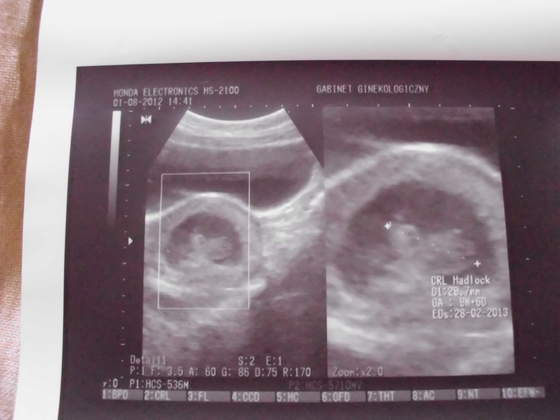

IMG_0453.jpg IMG_0454.jpgIMG_0455.jpgIMG_0456.jpg przedstawiam wszystkim cioteczką z bb moje małe szczęście:)

domikcw Noco ma byc to bedzie. Ale postarac sie warto. Kochana poza tym jakie cudowne zdjecia nam tu zarzuciłas:D piekna ta twoja fasolka!:*

Domik tak się cieszę, że u Was wszystko w porządku,że fasolinka pięknie się rozwija i tętni życiem:) uściski od cioci:)